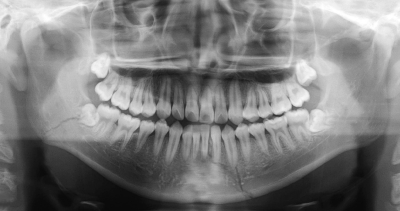

18 歳の男子。咬合異常を主訴として来院した。日前に自転車で転倒してオトガイ部を強打したという。初診時のエックス線画像を別に示す。

適切な治療法はどれか。2つ選べ。